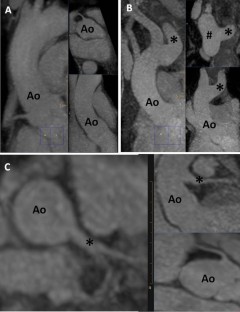

Fig. 4